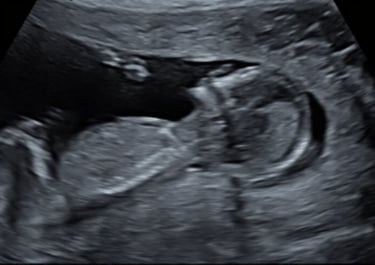

On 17 July, at 36 weeks, we went for a check-up. The ultrasound was perfect, no concerns.

The last weeks